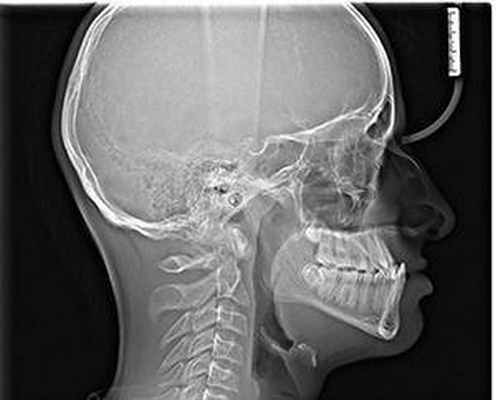

Турецким седлом называется анатомическая область в средней части черепа, напоминающая своей формой седло (этим и обусловлено название). В углублении седла располагается железа внутренней секреции – гипофиз, отвечающий за синтез ряда важнейших гормонов. Так как турецкое седло – костное образование, информацию о его состоянии можно получить с помощью рентгенологического исследования. Востребовано это исследование в гинекологической и нейрохирургической практике. Цель обследования. Исследование турецкого седла. Показания к исследованию. Детализация строения турецкого седла в случаях недостаточно четкого его изображения на снимках черепа в боковой проекции. Детализация патологических изменений турецкого седла. Подозрение на интраселлярные опухоли. Травматические повреждения турецкого седла. Подготовка к исследованию. Подготовка не требуется. Стандартные условия проведения исследования. Прицельная рентгенография турецкого седла производится в боковой проекции с обеих сторон в латеропозиции. Продолжительность исследования - 10-15 мин.

Рентгенографические снимки турецкого седла позволяют оценить размеры, форму, контуры кости, структуру костной ткани. По ним можно обнаружить:

Многие пациенты перед проведением процедуры желают знать: что показывает рентген турецкого седла? Метод достаточно эффективен и позволяет обнаружить любые патологические процессы, развивающиеся в области этой анатомической структуры. Рентгеновские снимки позволяют увидеть костную ткань, что даёт возможность определить не только форму, но и размеры наряду с контурами анатомического образования. В процессе расшифровки полученных данных врач сравнивает их с параметрами нормы по ряду критериев и делает соответствующий вывод.

Для того, чтобы определить размеры и форму турецкого седла по отношению к размерам и форме черепа, проводят боковую левую и правую обзорную рентгенографию черепа. Помимо этого, съёмку проводят в следующих проекциях в прямой лобно-носовой и прямой задней. Пациент принимает положение стоя возле рентгеновского аппарата, поворочиваясь лицом, спиной и боком, после чего проводится съёмка.

Что показывает снимок черепа?

По рентгеновским снимкам турецкого седла можно судить о его форме, структуре и размерах. Гипофиз также визуализируется на рентгене и о его опухоли могут свидетельствовать следующие признаки:

- местный или полный остеопороз стенок турецкого седла с сохранением нормальной структуры других костных образований;

- местная или полная атрофия стенок турецкого седла (на снимках можно заметить, как истончены стенки);

- местное или полное истончение клиновидных отростков турецкого седла;

- неравномерность контуров турецкого седла с внутренней стороны.

Описание снимка и заключение выполняет специалист-рентгенолог. При этом он определяет состояние стенки, а также форму и размеры турецкого седла. Если на снимке визуализируется опухоль, врач описывает её размеры, структуру и локализацию.

Рентгенография иногда может показать такую патологию, как «пустое турецкое седло». Признаки её могут быть следующими:

- дно во фронтальной плоскости симметрично;

- вертикальное увеличение седла замкнутой формы;

- двухконтурное дно на сагиттальном снимке.